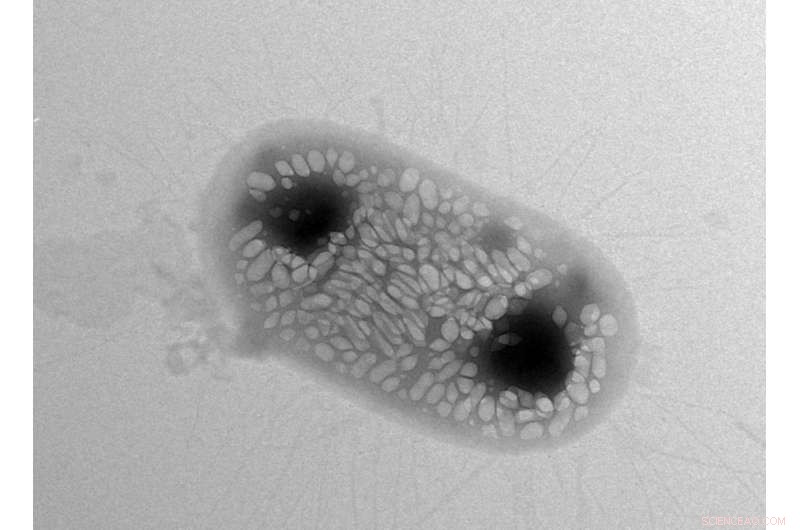

Transmission electron micrograph (TEM) image of a single commensal bacterium, E. coli Nissle 1917, which has been genetically engineered to express gas-filled protein nanostructures known as gas vesicles. The cell is approximately 2 micrometers in length, and the lighter-colored structures contained inside of it are individual gas vesicles. Credit: Anupama Lakshmanan/Caltech

In the 1966 science fiction film Fantastic Voyage, a submarine is shrunken down and injected into a scientist's body to repair a blood clot in his brain. While the movie may be still be fiction, researchers at Caltech are making strides in this direction: they have, for the first time, created bacterial cells with the ability to reflect sound waves, reminiscent of how submarines reflect sonar to reveal their locations.

Shapiro wants to solve this problem with ultrasound techniques because sound waves can travel deeper into bodies. He says he had a eureka moment about six years ago when he learned about gas-filled protein structures in water-dwelling bacteria that help regulate the organisms' buoyancy. Shapiro hypothesized that these structures, called gas vesicles, could bounce back sound waves in ways that make them distinguishable from other types of cells. Indeed, Shapiro and his colleagues demonstrated that the gas vesicles can be imaged with ultrasound in the guts and other tissues of mice.